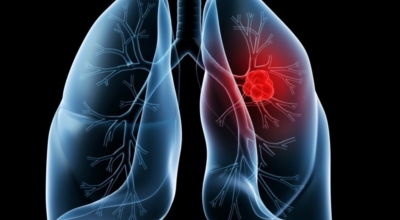

폐에 발생된 악성 종양을 말하며 오랜 기간 흡연해온 남성들에서 발병률이 높고 요즈음 각종 환경적인 요인의 영향과 간접흡연으로 흡연하지 않는 여성에서도 많이 발생하고 있습니다. 증상을 느껴 병원을 찾았을 때는 수술하기 늦은 경우가 많아 사망 가능성이 매우 높은 암입니다. 폐 자체에서 발생하거나 다른 장기에서 발생된 암이 폐로 전이되어 발생하기도 하고 특별한 초기 증상이 없는 경우가 많고 암이 진행된 후에도 공통적인 감기 증상인 기침과 가래 외의 특이 증상이 나타나지않아 증상만으로는 진단이 쉽지 않습니다.

폐암 검사는 X-ray를 통해서 검사하는데 , 크기가 작거나 구석에 위치한 경우 확인이 어려운 경우도 있답니다. 그리고 조직 검사를 통해서 정확한 진단을 하게 되어요. 폐암이 발견되면 종양의 크기나 전이 여부 , 위치에 따라서 수술 여부를 결정하게 됩니다.